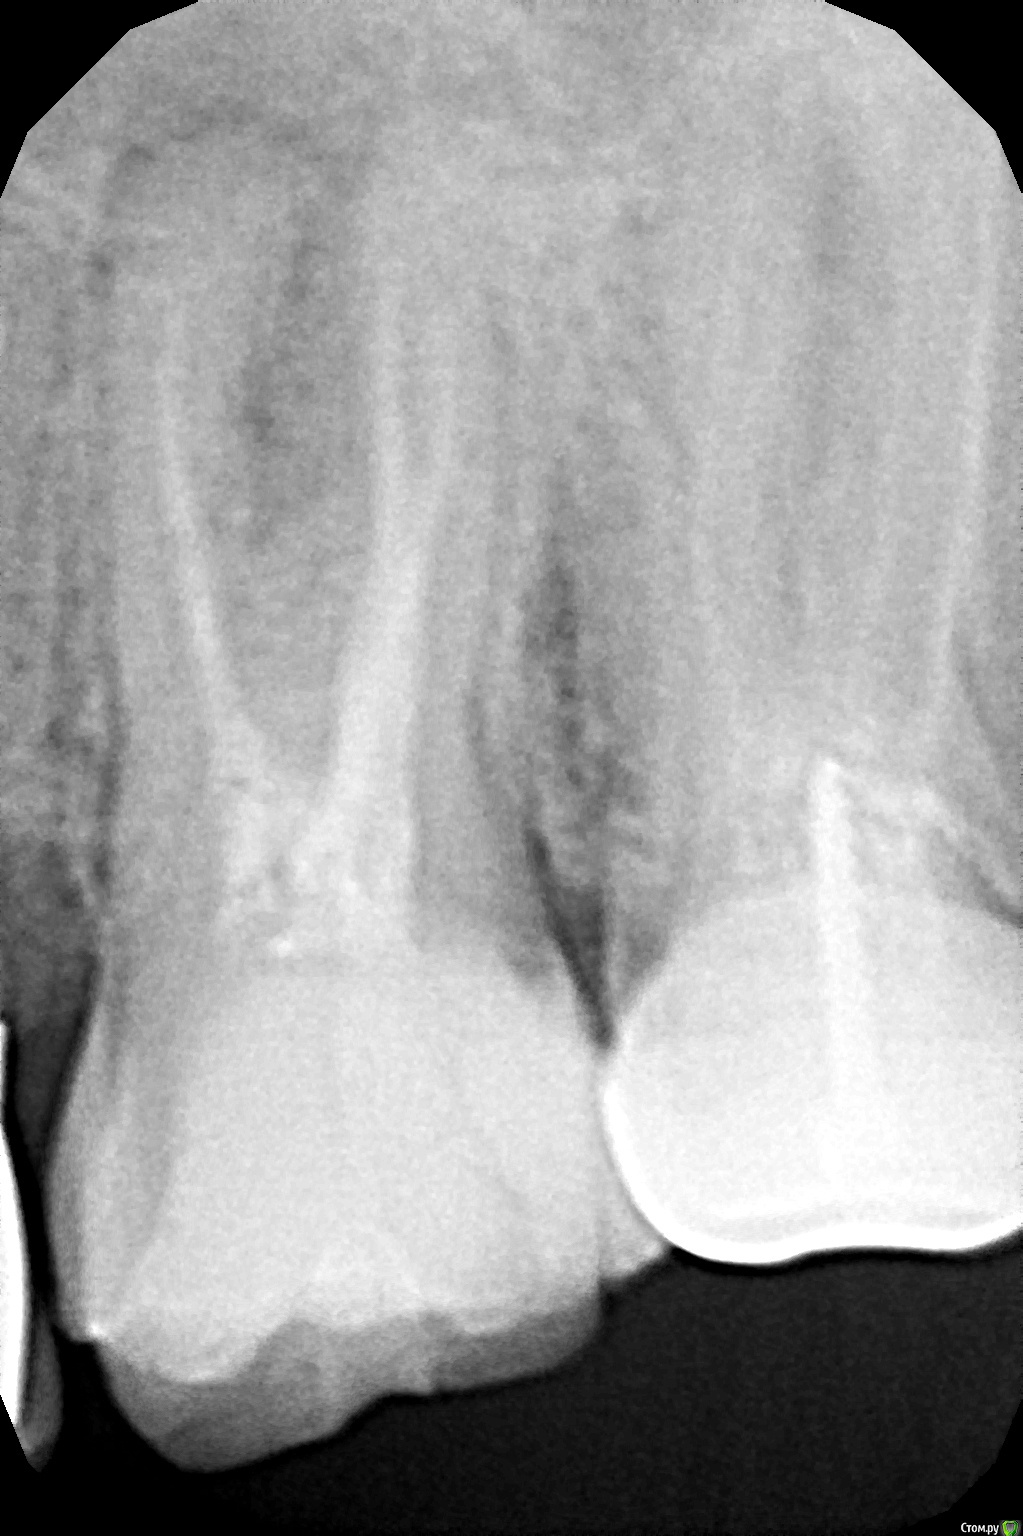

ИришАА Опубликовано 23 февраля, 2019 Поделиться Опубликовано 23 февраля, 2019 Здравствуйте. Треснула верхняя 6 она леченная уже. Врач говорит, тк треснул вместе с корнем и к тому же есть воспаление, то ни коронку ни вкладку делать нет смысла-удаление. Так ли это? И вопрос такой-как бы на общую тему-можно ли по панорамному снимку увидеть, что у зуба (корней) есть воспаление-как в моем случае? Или обязательно делать прицельный снимок? В разных клиниках просто мне делали по-разному и мне если честно не понятно. Спасибо. Ссылка на комментарий

___49___ Опубликовано 23 февраля, 2019 Поделиться Опубликовано 23 февраля, 2019 есть воспаление -это верно. треснул вместе с корнем по прицельному снимку или по ОПГ не всегда можно определить трещину. Ссылка на комментарий

DmitrySH Опубликовано 23 февраля, 2019 Поделиться Опубликовано 23 февраля, 2019 Трещину мы на снимке не видим ( это не значит что ее не может быть) Если Ваш врач очно видел трещину корня, тогда конечно удалять. Воспаление есть. И вопрос такой-как бы на общую тему-можно ли по панорамному снимку увидеть, что у зуба (корней) есть воспаление-как в моем случае? Можно но не всегда, прицельный тоже не всегда покажет. Самое объективное будет КТ 1 Ссылка на комментарий